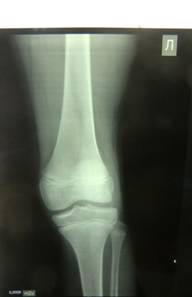

Артроз суставов у детей